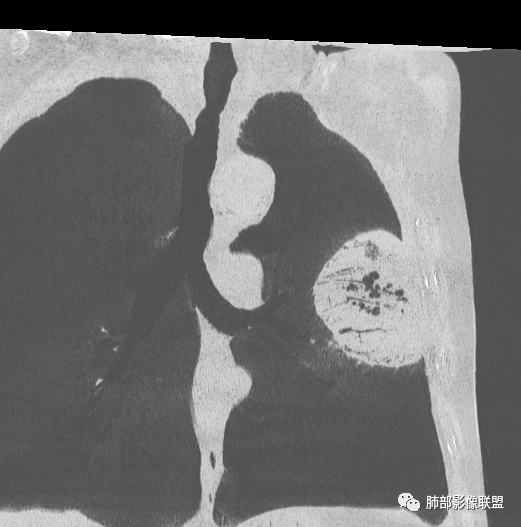

左肺上叶大肿块,膨胀性生长,边界清,密度较低,见部分坏死区,强化弱,肿块见支气管充气V扩张征,分布僵直,枯树枝特点,另一个重要特点血管造影征,淋巴瘤,肿块长轴与胸膜平行,与隐球菌鉴别,隐球荚膜抗原检查,明确诊断经皮肺穿刺。另胸膜钙化(问诊既往有无患胸膜炎病史)。

老年男性,糖尿病病史,消瘦、乏力三个月,影像表现左肺上叶胸膜下团块,有一定张力,内部疏松,可见支气管影及坏死区,增强病灶边缘环形强化,内部未见强化,考虑炎性肉芽肿病变,隐球?奴卡?放线菌?鉴别淋巴瘤。

左肺上叶胸膜下肿块,宽基底与胸膜相连,跨叶裂,边缘清晰膨隆,其内支气管充气,部分扩张、僵直,无明显强化,血管造影征,考虑淋巴瘤,鉴别腺癌

左肺胸膜下巨大占位,跨叶裂,宽基底与胸膜相连,胸膜钙化,平扫密度较低,强化不明显,可见内部血管显影,支气管充气征和扩张,考虑为恶性,倾向于淋巴瘤

左肺上叶胸膜下肿块,膨胀性生长,边界清晰,密度不均部分坏死,未见强化,病灶内支气管迂曲扩张,病灶长轴与胸膜平行,胸膜下脂肪间隙存在,胸膜钙化,考虑放线菌?毛霉?鉴别淋巴瘤

支持淋巴瘤,左上肺大肿块,有分叶,边缘光整,病灶内密度不均,可见支气管扩张征,增强后可见血管影征。周围肺野清晰。

左肺上叶肿块,宽基底与胸膜相连,跨叶裂,边缘清晰膨隆,可见小分叶,其内支气管充气,部分扩张、僵直,呈枯枝征,支气管达边征,增强无明显强化,可见血管造影征,考虑恶性病变,淋巴瘤,鉴别粘液腺癌。

糖尿病史,慢性病程,左肺巨大肿块,跨叶生长,肿块近端可见充气支气管征及悬浮气泡,轻度圴匀强化,病变长轴与胸膜平行,炎性标志物正常,考虑放线菌,其次淋巴瘤

大肿块,边缘光滑,深分叶

近端支气管堵塞、推移为主

部分类似于脐凹征

内部支气管扩张

肺动脉推移为主,边缘部分进入

4)密度:肿块平扫为软组织密度,由于体积较大,内部常见大片状坏死,可出现不规则厚壁空洞或坏死内多发无壁小空洞,坏死多不均匀:坏死灶内可见如柳絮样的斑片样强化灶,坏死边缘与非坏死区分界不清本例坏死较明显,密度不均匀。

5)肿瘤强化方式:肺部恶性肿瘤强化程度与其血供丰富程度相关,血供丰富多强化明显,反之则较差。由于PSC 周边实性部分富血供及内部黏液变性、坏死,增强后肿块多数呈轻-中度边缘环形强化或不均匀小斑片状强化。国外学者对照病理发现肿瘤细胞或胶原组织增强扫描时强化,无强化的低密度区代表了黏液样变性区和出血坏死区。